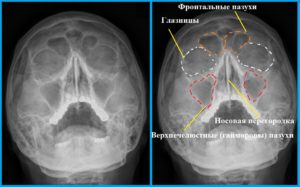

Рентген назначают при подозрениях на такие заболевания:

• синусит;

• гайморит;

• переломы костей носа.

ЛОР может рекомендовать беременной сделать снимок пазух носа, но только с середины второго триместра.

Некоторые специалисты утверждают, что рентген на носу не должен принести вред малышу, так как обследуемая площадь небольшая, да и доза облучения минимальна.

Обследования с наименьшей опасностью В категорию минимально опасных относятся следующие обследования: рентген носа и зубов.

Для проведения подобных манипуляций применяется специальное оборудование, охватывающее гораздо меньшую площадь по сравнению со стандартными снимками.